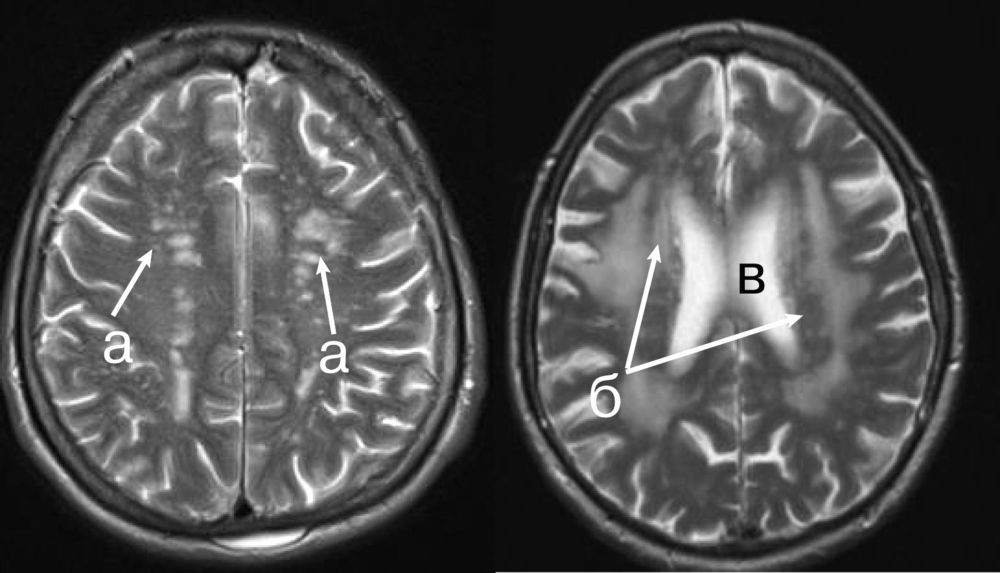

Хроническая ишемия головного мозга и лейкоареоз: симптомы и лечение